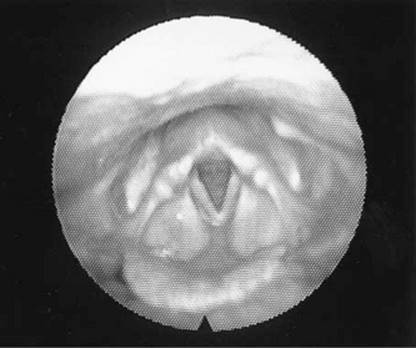

The voroscope (Fig 2.3) has revolutionised the ENT — head and neck examination. A good headlight from theatre will often suffice. Sometimes only a light source and head mirror are available.

Figure 2.3 Voroscope

Photos courtesy of Mr Sarin Wongprasartsuk

Flexible nasal endoscopy has also revolutionised the diagnosis of ENT — head and neck conditions. It has become an integral part of the examination and enabled office-based diagnosis. There are many hidden areas in ENT — head and neck examination and the nasoendoscope has permitted access to the internal nose, sinus outflow tracts, post-nasal space, larynx, hypopharynx, tongue base and sometimes the proximal oesophagus (Fig 2.4).

Figure 2.4 Nasolaryngoscope

From Dhillon & East, 2006